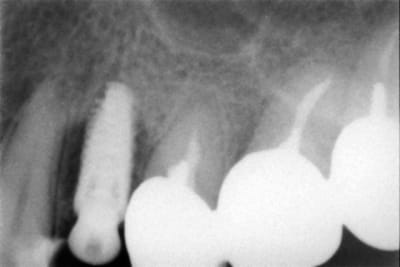

Un "vieux cas" LEONE qui se passe bien malgré des conditions de départ et de chirurgie pas au mieux! 4 ans déjà et aspect sympa très stable dans le temps. une de mes extractions implantation immédiate en site "pas idéal".La chronologie en rx.

Janvier 2008 vzunxr - Eugenol

Octobre 2008 ehmsfj - Eugenol

Mars 2008 jt5qx2 - Eugenol

Novembre 2011 ane4ar - Eugenol